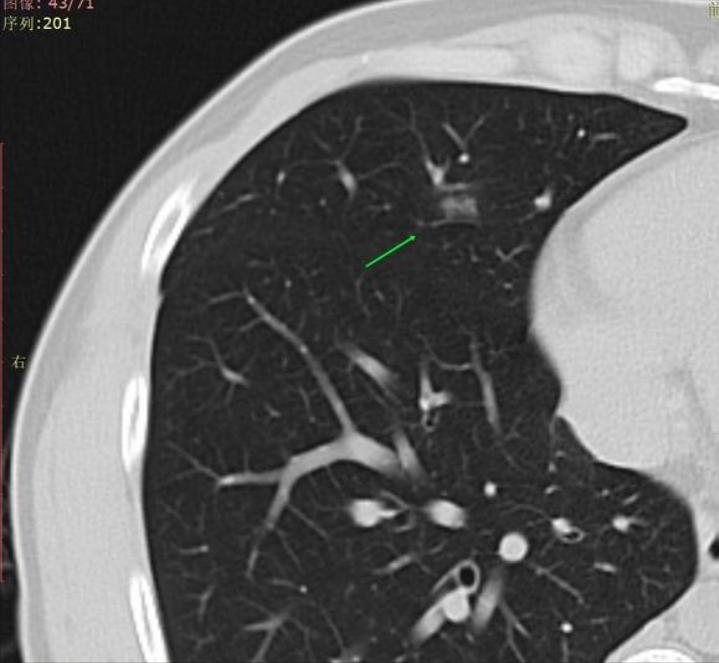

这是刚查出的结节。

在夭夭姐的教导下,我开始尝试发帖,很幸运连续发了三个帖子都得到了主任的回复(说声抱歉,因为着急帖子不太规范)。主任叫我拿2020年12月29日的CT影像对照,看看是不是漏诊了。我立刻重新发帖,贴上2020年的老片对照,主任回复我:“是炎症,口服拜复乐9天,夏枯草口服液1个月,会消。”我决定放下心里的焦虑,信任主任,安心消炎等待复查。